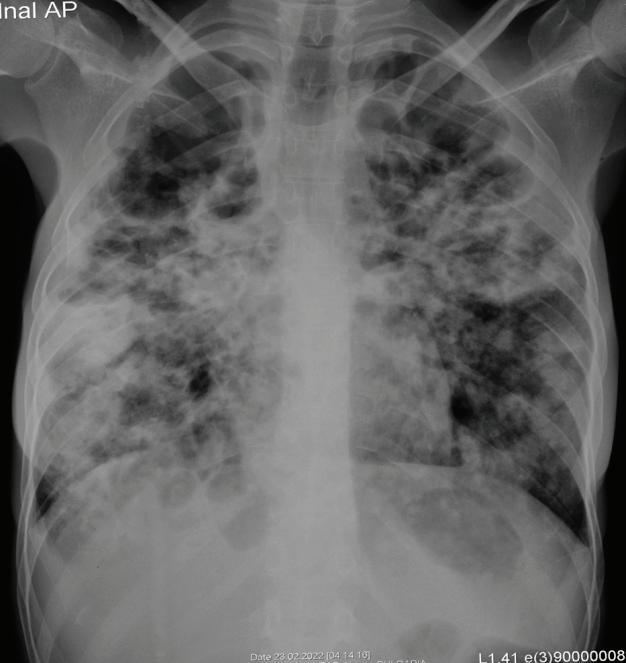

СИМПТОМИ НА ГРИП Инфектираните с грипен вирус съобщават за внезапно настъпила треска, кашлица, възпалено гърло, запушен нос, болки в мускулите, главоболие, умора. Повръщане и диария се среща по-често при малките деца. Според някои проучвания грип А протича по-ле -

ко, а грипният вирус тип В води по-често до усложнения от страна на дихателна, сърдечно-съдова и нервна система. Тежката първична грипна пневмония протича със силно изразена токсикоза, диспнея, цианоза, тахикардия. Аускултаторната находка е по-често негативна. Рентгеновото изследване установява двустранни белодробни изменения, характерни за респираторен дистрес синдром, но без консолидиране. Състоянието на болните не се повлиява от антибиотичната терапия. Може да доведе до фатален изход както при деца, така и при възрастни. Вторичната бактериална пневмония често се предизвиква от пневмококи, стафилококи и други бактерии[7,9]. За нея се мисли при повишаване на температурата след около 10 дни след началото на грипна инфекция. Налице са аускултаторна находка в белите дробове и рентгенови изменения. Антибиотичното лечение повлиява благоприятно общото състояние и локалните промени в белодробния паренхим. Възможна е и смесена пневмония. Усложненията са чести при болни с хронични белодробни, сърдечни и метаболитни заболявания, при имуносупресирани лица. Немалко от тези групи болни показват резистентност към антивирусните медикаменти. В детска възраст като усложнение често се среща грипозния круп. Протича с дрезгава, лаеща кашлица, затруднено дишане, неспокойствие. По-често се причинява от парагрипен вирус тип 1 или 3 или респираторно-синцитиален вирус[1]

П. Павлов Медицински Университет - Плевен

Пневмонии, придобити в обществото – съвременни

решения в клиничната практика

Ключови думи: Пневмонии, тенденции, поведение.

Пневмонията е едно от най-големите открития на клиничната медицина. Диагнозата и лечението й в днешно време се усложняват от появата на нови, непознати патогени, разширяващата се антибиотична резистентност, увеличаващата се популация на имунокомпрометирани пациенти, модерни диагностични методи и антимикробни средства.